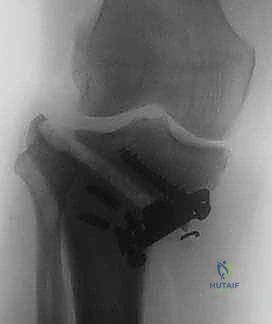

خطوات الجراحة: رحلة دقيقة داخل غرفة العمليات

تُجرى عملية قطع عظم الظنبوب القاصي تحت التخدير النصفي أو الكلي، وتستغرق عادة من ساعة إلى ساعتين. إليك التفاصيل الدقيقة لما يحدث داخل غرفة العمليات تحت إشراف الأستاذ الدكتور محمد هطيف:

3. إجراء القطع العظمي (The Osteotomy):

باستخدام أدوات دقيقة ومناشير جراحية متطورة، يتم عمل قطع غير مكتمل في عظمة الساق. هناك طريقتان رئيسيتان:

* الشق المفتوح (Opening Wedge): يتم فتح العظم من الداخل وإضافة طعم عظمي (صناعي أو طبيعي) لملء الفراغ وتعديل الزاوية. وهي الطريقة الأكثر شيوعاً حالياً.

* الشق المغلق (Closing Wedge): يتم إزالة إسفين (مثلث) صغير من العظم من الجهة الخارجية وإغلاق الفراغ.

4. تعديل المحور:

يتم فتح العظم تدريجياً وببطء شديد حتى الوصول إلى الزاوية التي تم حسابها في التخطيط الرقمي قبل الجراحة.